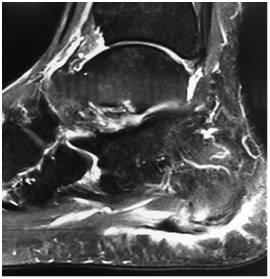

After the 5th week of rehabilitation without jumping restrictions, magnetic resonance (MR) control was requested, showing a thickening of the plantar fascia next to its calcaneal insertion with a maximum thickness of 9 mm showing increased signal intensity with healing of its fibers in its portion More medial (Figure 4) (Figure 5). There is evidence of plantar fascia thickening next to its calcaneal insertion with 9 mm of thickness. After confirming the healing process, the athlete was available to the technical committee for training and games at the end of the 5th rehabilitation week.

Figure 4, 5 Magnetic resonance control with T2-weighted multiplanar FAT SAT sequences.